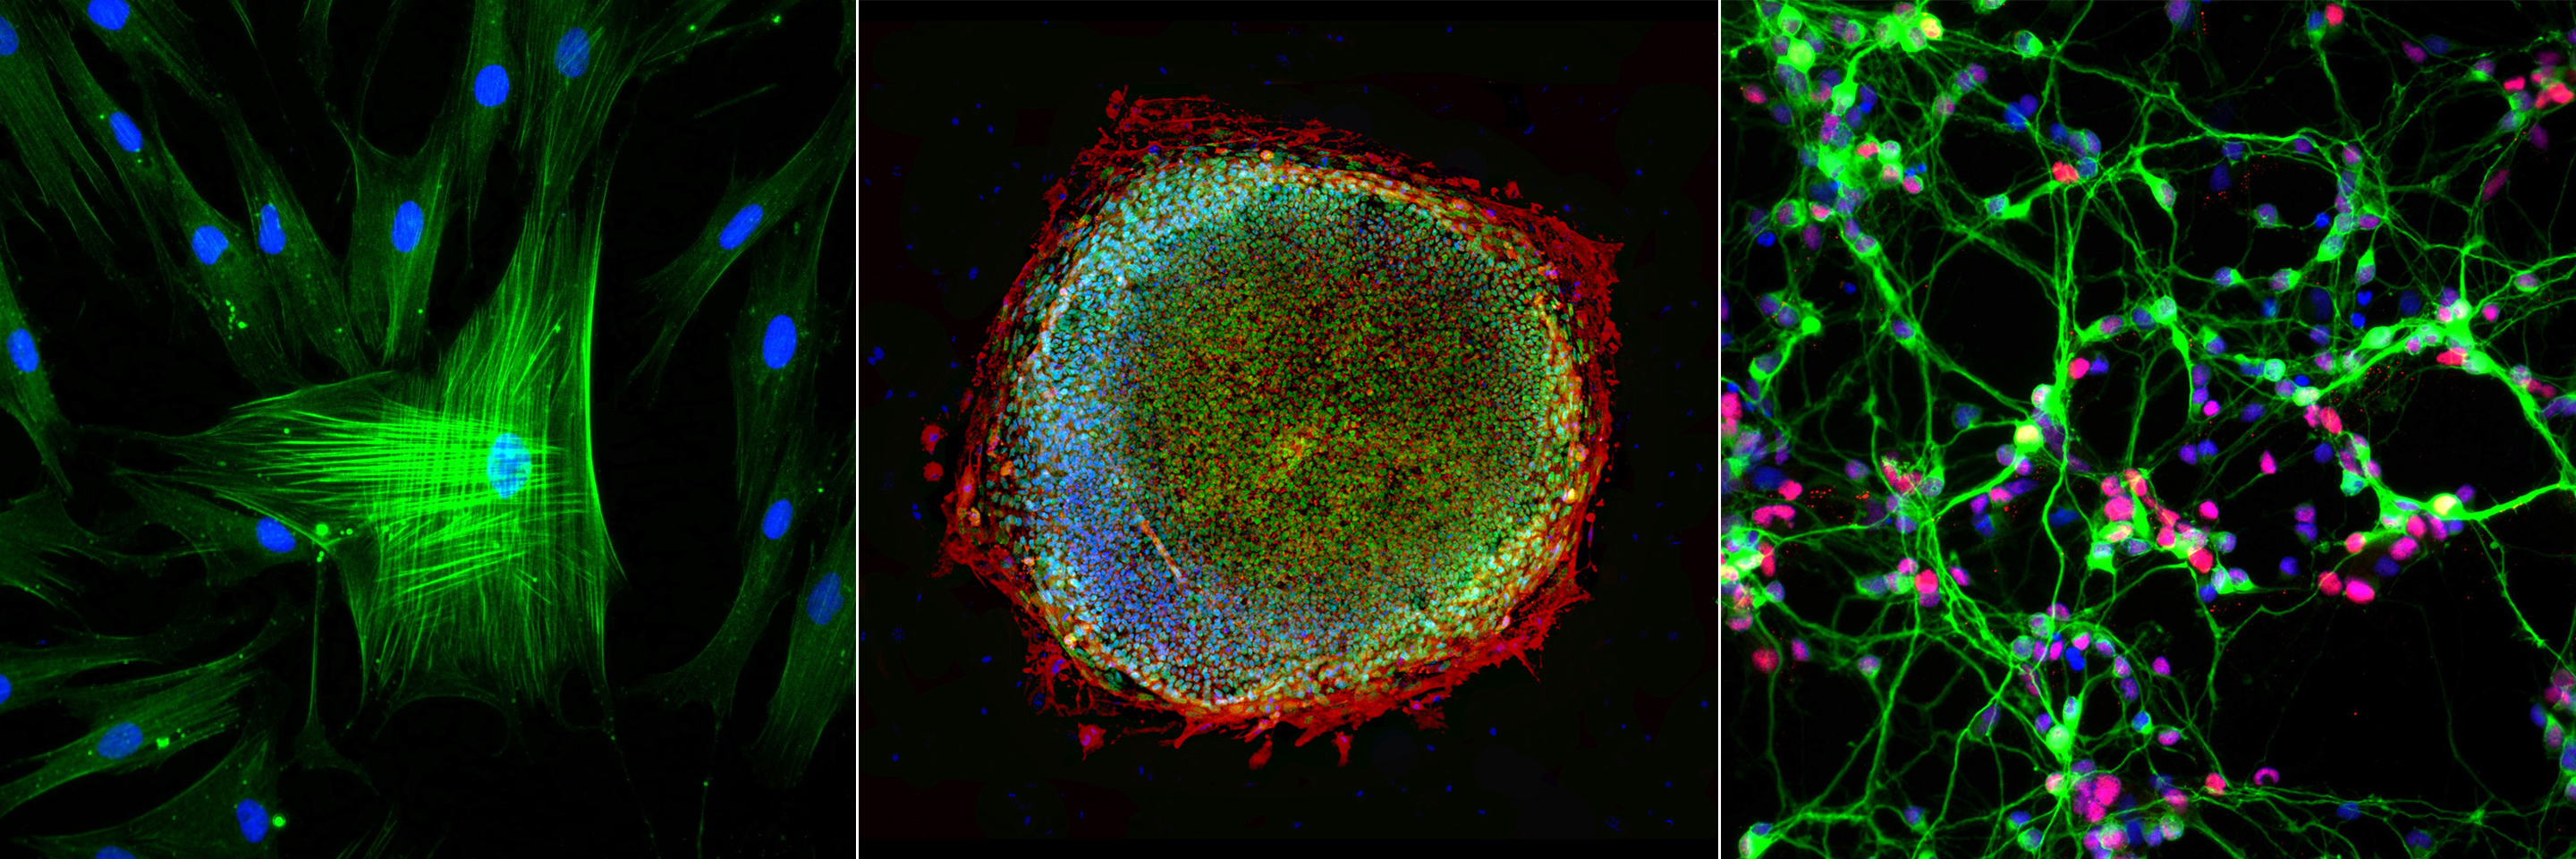

科學家現在可以從人類胚胎干細胞 (ESC) 和人類誘導多能干細胞 (iPSC) 中制造產生多巴胺的神經元。由人類ESC和iPSC制成的神經元成熟為人類產生多巴胺的神經元,在移植到小鼠、大鼠和猴子PD模型后存活并發揮功能。

了解疾病:科學家們正在從PD患者身上提取細胞,并在實驗室中使用這些干細胞來產生患有這種疾病的神經元。患病的神經元是研究帕金森病發病機制的有力工具。

開發新藥:通過從帕金森病患者身上提取細胞,并在實驗室中使用這些干細胞產生患病的神經元,科學家們可以篩選出可以開發成治療該疾病的新藥的物質。

科學家現在可以從人類干細胞中制造產生多巴胺的神經元。由人類干細胞制成的神經元成熟為人類產生多巴胺的神經元,在將它們移植到大鼠、小鼠和猴子體內后存活并發揮作用。需要更多的研究來確定這種方法是否適用于PD患者。

迄今為止,我們對PD動物模型的研究表明,由ESC和iPSC制成的人多巴胺神經元可以成熟為所需的細胞類型,在PD動物模型中成熟并發揮多巴胺神經元的功能,重要的是沒有顯示出任何導致過度的能力-增長。最近,我們還證明了我們在實驗室中制造的多巴胺神經元與人類胎兒的多巴胺神經元幾乎相同。我們的協議允許我們以非常精確的方式從胚胎干細胞中產生大量這些人類多巴胺神經元——從而產生更純凈的臨床級細胞群,用于臨床試驗。

科學家們正在使用iPS細胞來研究使某些人易患帕金森病的遺傳問題。TiloKunath在英國愛丁堡的研究小組正在通過從具有已知的PD遺傳原因的母女身上制造iPS細胞來做到這一點。母親患有帕金森病,但她的女兒并沒有遺傳到這種遺傳問題。通過比較不同iPS細胞產生神經元的能力并仔細檢查這些神經元,研究人員希望更多地了解這種疾病的發病機制,并找到治療它的新藥。